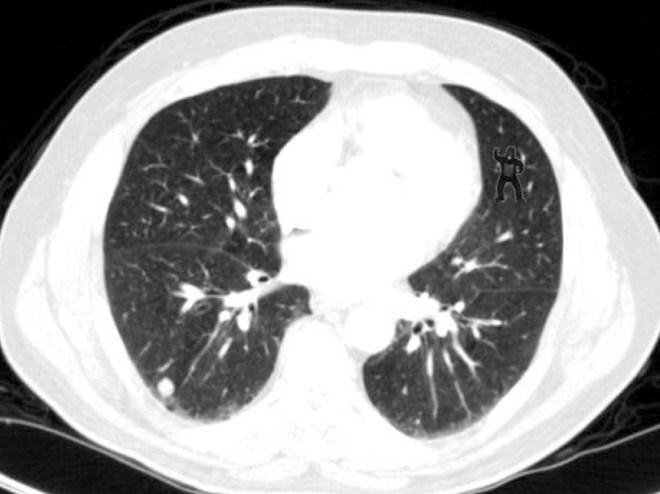

In an attempt to explain why radiologists sometimes miss important aspects of the images they review, Trafton Drew and Jeremy Wolfe recreated a famous attention study using the above image. Alix Spiegel summarizes:

He took a picture of a man in a gorilla suit shaking his fist, and he superimposed that image on a series of slides that radiologists typically look at when they’re searching for cancer. He then asked a bunch of radiologists to review the slides of lungs for cancerous nodules. He wanted to see if they would notice a gorilla the size of a matchbook glaring angrily at them from inside the slide. But they didn’t: 83 percent of the radiologists missed it, Drew says.

(Image from Trafton Drew and Jeremy Wolfe)